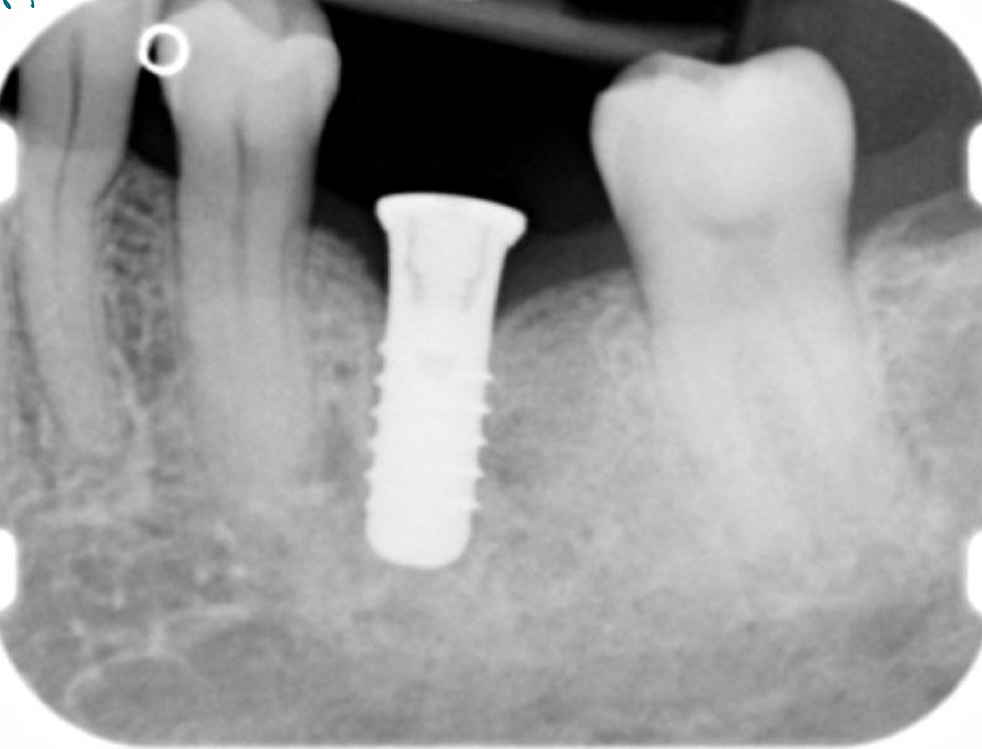

Unloaded implant

Implant loaded